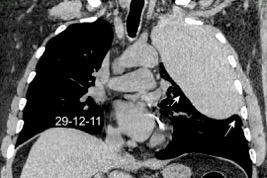

Marzo 2014: Perforación longitudinal distal secundaria a episodio de vómito (síndrome de Boerhaave). Derrame pleural izdo. que evoluciona a empiema.

Wang C-T et al. Tension hydropneumothorax in a Boerhaave syndrome patient: A case report . World J Emerg Med, 2021. Katabathina V et al. Nonvascular, nontraumatic mediastinal emergencies in adults:a comprehensive review of imaging findings. Radiographics. 2011.